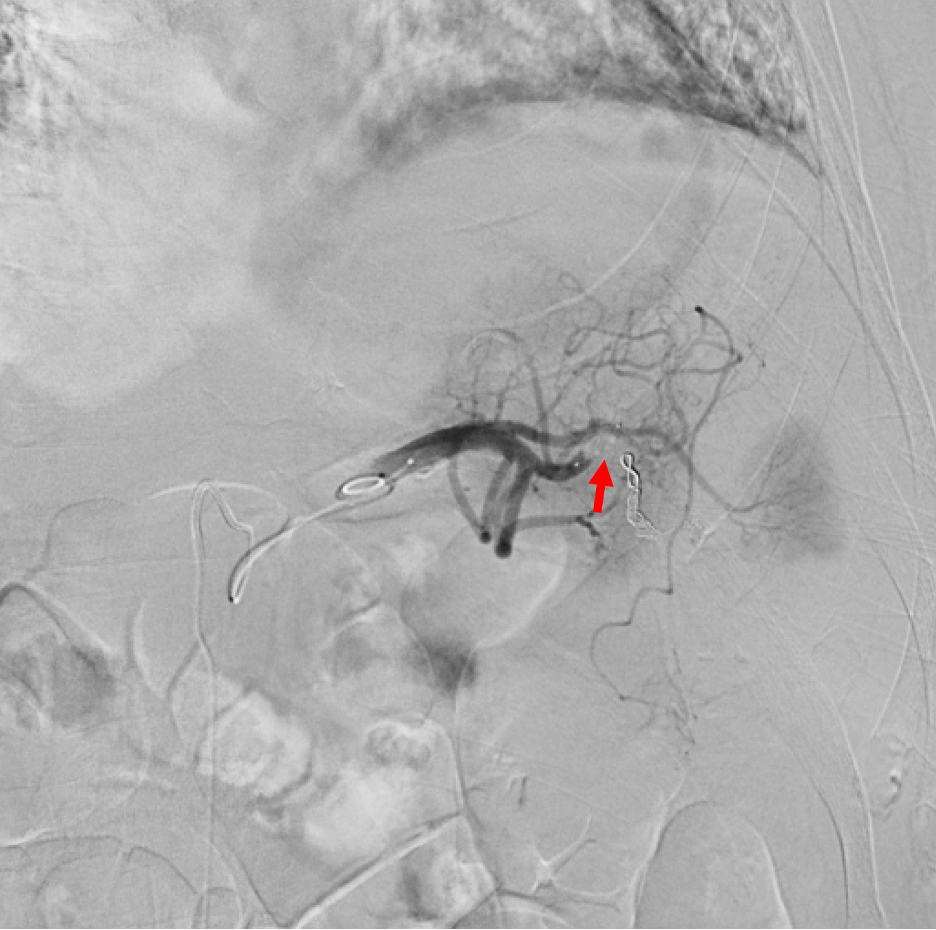

Treatment and management. The patient was stabilized with intravenous fluids and albumin and did not require a blood transfusion. Upon confirming bleeding from the spleen, an angiogram was immediately performed which identified a 7 mm pseudoaneurysm in the spleen's lower pole with active bleeding (Figure 4). Using ultrasound-guided access through the right common femoral artery, the catheter was directed to the splenic artery. The angiography pinpointed a descending branch feeding the pseudoaneurysm. Embolization of the descending branch was performed using gelatin sponge followed by fibered coils, both of which were visible in a post-procedure fluoroscopy (Figure 5). A microvascular plug was positioned proximally in the branch. Subsequent angiography confirmed the occluded arterial branch, absence of pseudoaneurysm filling, and cessation of bleeding (Figure 6).

Figure 5. Post-embolization angiography with visualization of coil, microvascular plug, and gelatin sponge placed intra-arterially (solid arrow).

Figure 6. Post-embolization angiography demonstrating occlusion of a descending branch of the splenic artery (solid arrow), no active bleeding, and no residual filling of the pseudoaneurysm.